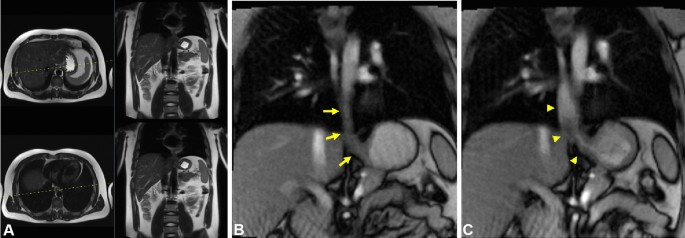

Real-time MRI

Real-time MRI parameters with undersampled radial FLASH and a corresponding examination protocol for assessment of the esophagus and EGJ have been extensively described in previous studies7,9,10,12. Ultra-fast spin echo (HASTE) and balanced steady-state gradient echo (TRUFI) MRI sequences in axial and coronal planes served as planning sequences for sagittal real-time MRI acquisitions of the middle and lower esophagus and EGJ. Next followed a real-time acquisition of bolus transit through the lower esophagus and EGJ in coronal plane. These recordings were followed by real-time MRI acquisitions of the same planes during Valsalva maneuver. In case of insufficient visualization of the esophagus or EGJ, real-time MRI acquisitions were repeated with optimized plane orientation if necessary.

Imaging examples highlighting the plane orientations are presented in Figs. 1 and 2. Further examples of plane orientation in patients with challenging EGJ anatomy are provided in Figures S1 and S2 of the supplemental material. The real-time MRI protocol of the esophagus and EGJ is summarized in Table 1.